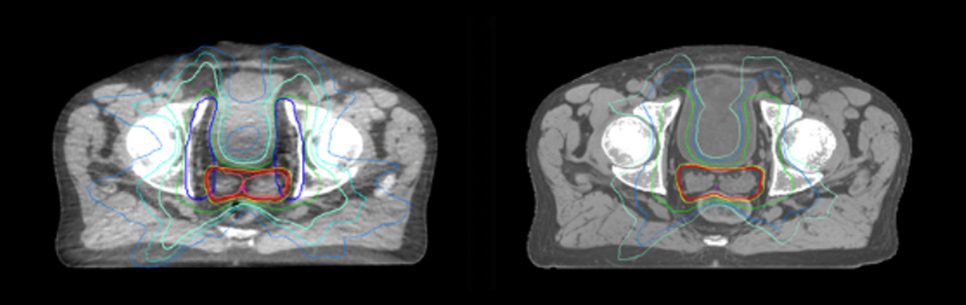

Evaluation of MRCAT dosimetric accuracy

Dosimetric equivalence validation was performed on 43 patient cases by comparing MRCAT-based dose plans overlaid on CBCT image dataset and on the corresponding MRCAT image dataset. Mr. Bolard and Dr. Champion found good agreement between MRCAT-based and CT-based dose calculations, with a mean dose ratio of 1.007 (0.991-1.014). The 3D gamma score was greater than 95% (95.2-99.0%) for all plans checked. A poster on this work was accepted for presentation at ESTRO 2020.

Dataset MRCAT image

Dose plans overlaid on CBCT image dataset (left) and on MRCAT image dataset (right).